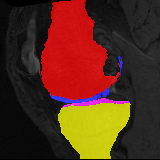

Moving Target Mono-0 Mono-5 DA-1 DA-5 Mono-200 Refer to caption Refer to caption Refer to caption Refer to caption Refer to caption Refer to caption Refer to caption Refer to caption Refer to caption Refer to caption Refer to caption Refer to caption Refer to caption Refer to caption

Figure 2:  Examples of knee MRI registration (top) and brain MRI segmentation (bottom) results. Top: The first two columns are the moving image/segmentation and the target image/segmentation followed by the warped moving images (with deformation grids)/segmentations by different models. Bottom left to right: original image, manual segmentation, and predictions of various models. Mono-i𝑖i and DA-i𝑖i represent the mono- and DA models with i𝑖i manual segmentations respectively.

Results: All trained networks are evaluated using Dice overlap scores between predictions and the manual segmentations for the segmentation network, or between the warped moving segmentations and the target segmentations for the registration network. Tabs. 1 and 2 show results for the knee and brain MRI experiments respectively in Dice scores (%). Fig. 2 shows examples of knee MRI registrations and brain MRI segmentations.

Knee results: On knee MRIs, our method improves segmentation scores over separately learned networks by about 1.2 and 0.5, and registration scores increase by about 3.1 and 3.0, when training with 5 and 10 manual segmentation respectively. Especially for the challenging cartilage structures, our joint learning boosts segmentation by 1.4 and 0.7, and registration by 5.5 and 5.2 for N=5 and N=10 respectively.

Qualitative results: DA achieves more anatomically consistent registrations than the mono-networks on the knee (Fig. 2) and Brain MRI samples (see supplementary material).

Figure 4: Examples of brain MRI registration (top) and knee MRI segmentation (bottom) results. Top: The first two columns are the moving image/segmentation and the target image/segmentation followed by the warped moving images/segmentations by different models. Bottom left to right: original image, manual segmentation, and predictions of various models. Mono-i𝑖i and DA-i𝑖i represent the mono- and DA models trained with i𝑖i manual segmentations respectively.